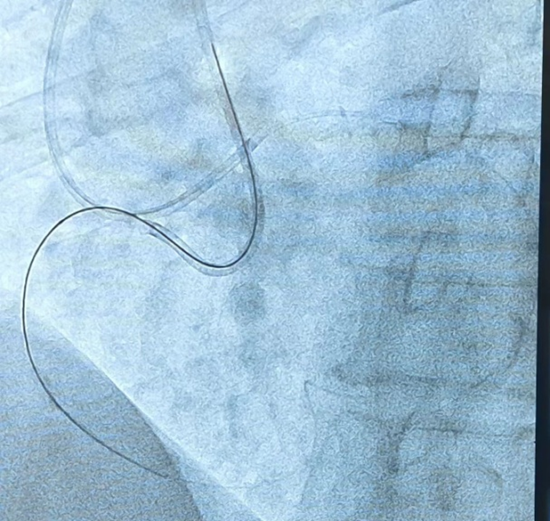

通过严重迂曲心外膜通道的逆向导丝有了逆向导丝指引,术者再次尝试正向进入靶病变,应用 CART 技术,通过手感对斑块软硬程度的认知,经过延长导管与微导管配合,正向反复尝试、升级导丝,最终使用导丝正向通过夹层通路。正向导丝与逆向导丝慢慢会师,双向导丝交汇,多体位证实导丝无限接近。继续操作正向导丝缓慢前行,顺利进入逆向微导管内,并送入 AV 支。

正向导丝进入逆向微导管经过 IVUS 观察,近端纤维帽提示 360 度环形钙化,应用预扩球囊、切割球囊及非顺应性球囊处理后,顺利植入支架,复查 IVUS 提示支架膨胀贴壁良好,无血肿、夹层形成,血流 TIMI 3 级。